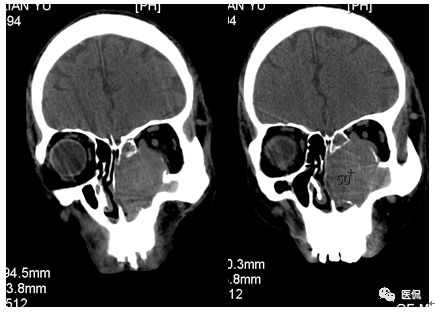

增强动脉期

增强静脉期

CT平扫及增强示:左侧上颌窦及鼻腔可见软组织密度影,呈膨胀性生长,周围骨质压迫性吸收破坏,累及左眶,病灶密度不均匀,周边区可见点状钙化,增动脉期轻度强化,局部见小灶性稍高密度区,静脉期病灶内见不均匀明显强化,CT值最高达117HU,延迟期强化范围有所增大。

本例病灶较大,周围骨质可见吸收破坏,并累及眼眶,病灶内少量钙化,增强扫描具有一定特征性,表现为动脉期轻度强化,局部见小灶性稍高密度区,静脉期病灶局部呈明显强化,CT值最高达117HU,延迟期强化范围有所增大,呈延迟渐进性强化的特点,推测为病灶内出血所致。